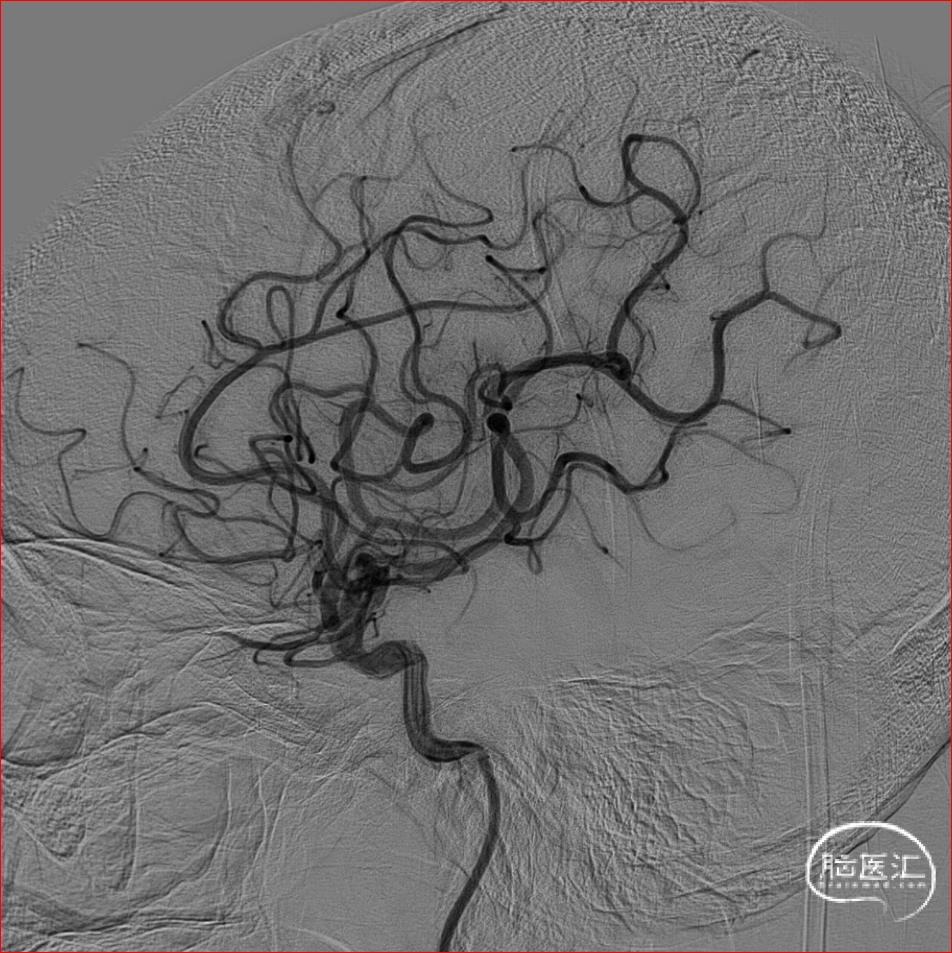

术前CTA可知责任血管为右侧大脑中动脉,遂在泥鳅导丝及4F多功能管的引导下,直接将8F导引导管送至右侧颈内动脉C1段,造影示右侧大脑中动脉M1远端下干闭塞,同侧大脑前动脉通过脑膜支向大脑中动脉供血区代偿供血,代偿ASTRIN分级2级,将SKATHI远端通路导管送至颈内动脉C4段,随后微导管(Rebar 18)在微导丝(Synchro 14)辅助下,小心通过大脑中动脉下干闭塞段至M2段,再将SKATHI远端通路导管顺利送至大脑中动脉闭塞段近端,并抵住血栓近端,撤出微导丝及微导管,用50ml注射器保持负压吸引抽吸导管,约1分钟后缓慢回撤中间导管至颈内动脉C4段,抽出多枚栓子,复查造影见右侧大脑中动脉各分支完全显影,TICI3级,血流速度正常。

术后即刻影像

术后72小时MRA:右侧大脑中动脉血流复通,双侧血管对称。